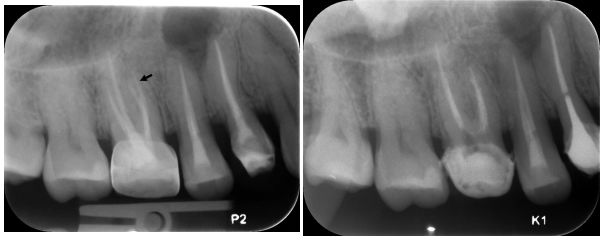

5.下圖為使用不同偏移角度對上顎右側後牙所拍攝的X光片。依據Weine的分類定義,右上第二小臼齒的根管形 態是屬於那一型?而箭頭所指的是第一大臼齒的那個根管?

(A)第二型根管形態,近心頰側根管(MB canal) (B)第二型根管形態,第二近心頰側根管(MB2 canal) (C)第三型根管形態,近心頰側根管(MB canal) (D)第三型根管形態,第二近心頰側根管(MB2 canal)